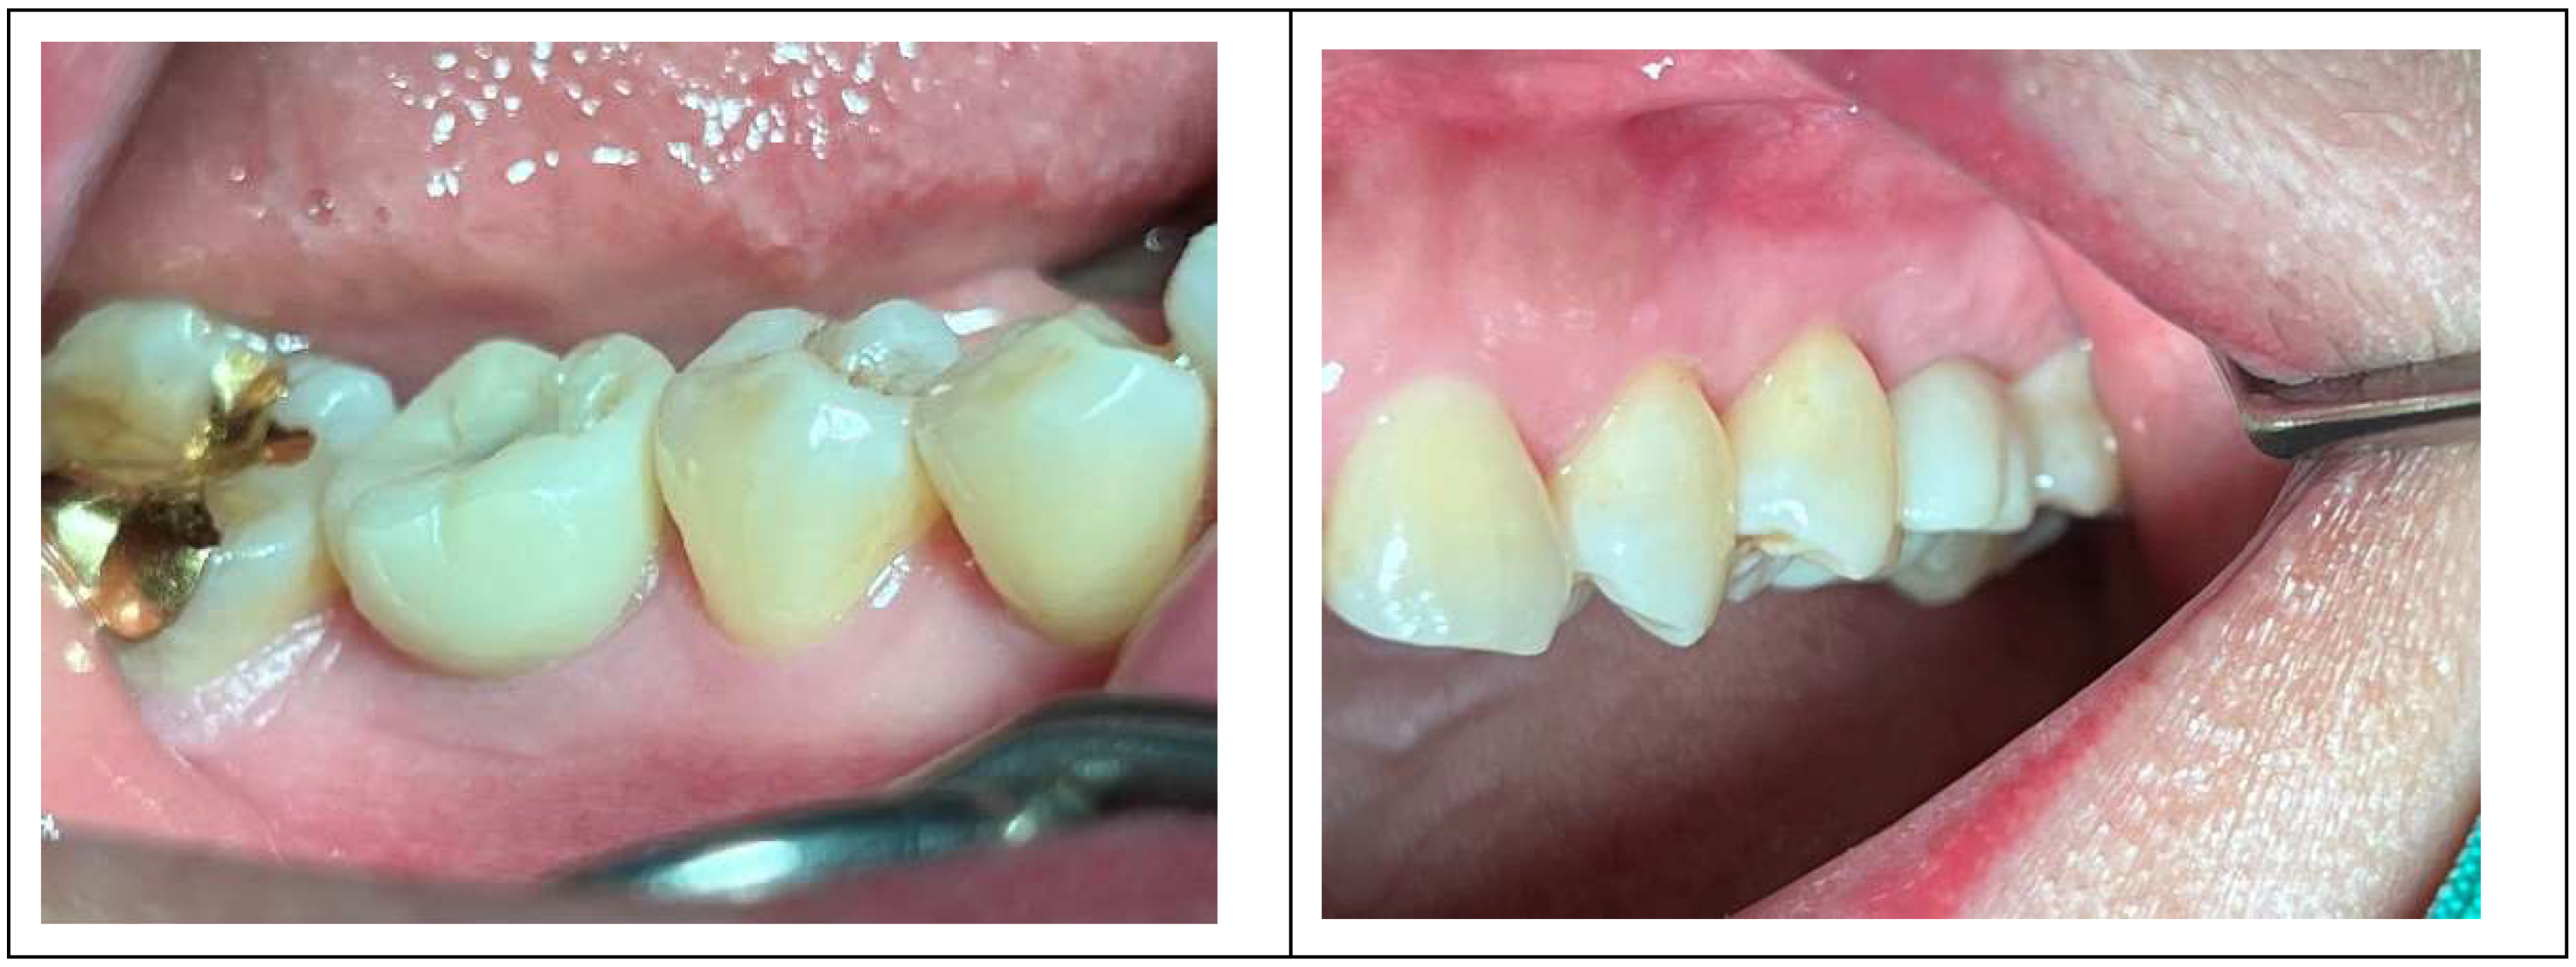

Following the restoration remake, the patient reported no further discomfort, including gingival bleeding, swelling, or food impaction. Clinical examination confirmed healthy peri-implant soft tissue with no radiographic bone resorption. Probing with the Implant Paper Point Probe (IPPP) (Sure Endo, Seoul, South Korea) at a yield strength of 0.35 N showed a consistent depth of less than 1 mm, with no bleeding, confirming the successful resolution of peri-implant mucositis.

Figure 6 compares the restorations before and after revision, highlighting profile differences. It also includes a post-revision panoramic X-ray and clinical photographs taken on October 31, 2022 (

Figure 6).

Figure 6.

The upper left image presents a comparison of the two restorations before and after the revision, while the upper right image shows a panoramic X-ray taken post-revision. The lower two images display the clinical appearance of the upper left first molar implant restoration following the revision procedure conducted on October 31, 2022.